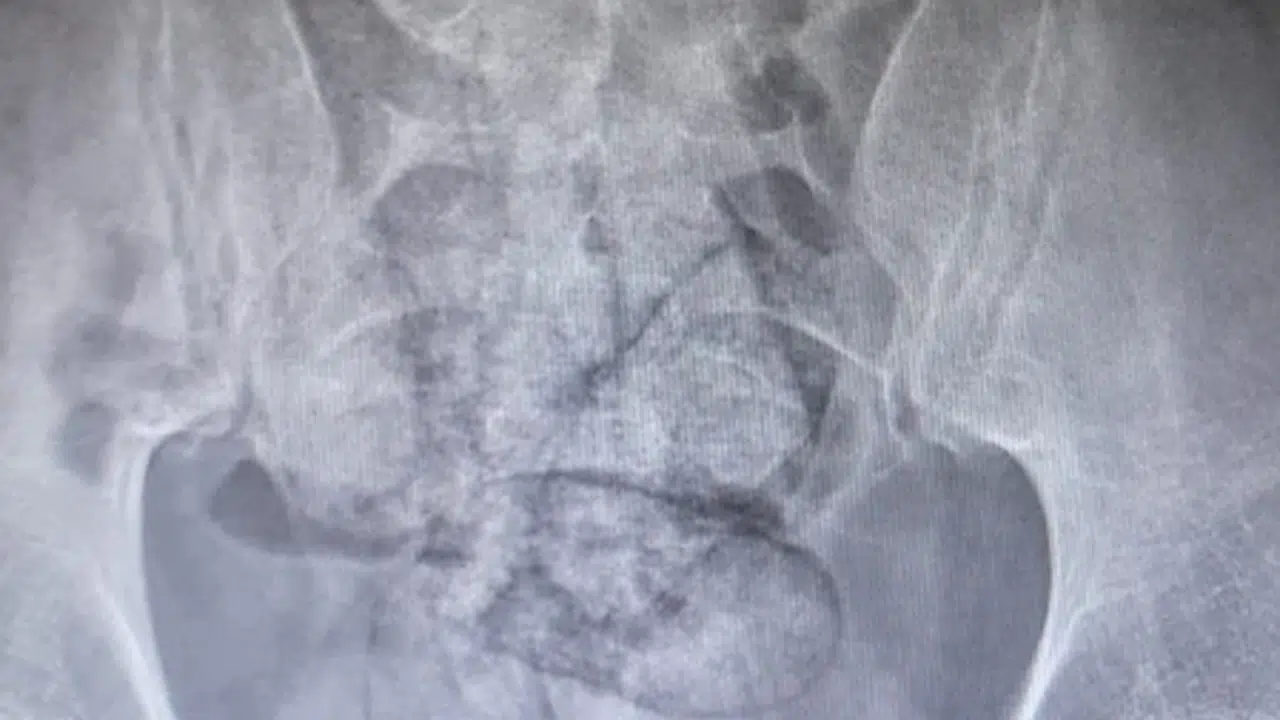

ARTVİN, (DHA)- ARTVİN’de bağırsağından 350 gram metamfetamin çıkan İran uyruklu F.R. (43) gözaltına alındı.

İl jandarma ekipleri, takip ettikleri İran uyruklu şüpheliyi dün saat 02.00 sıralarında Çayağzı Mahallesi’nde durdurdu. Üzerinde yapılan aramada herhangi bir olumsuzluğa rastlanmayan F.R., detaylı kontrol için hastaneye götürüldü. Artvin Devlet Hastanesi’nde tomografisi çekilen şüphelinin bağırsaklarında 10 paket halinde uyuşturucu madde taşıdığı belirlendi. Şüphelinin hayati tehlike oluşturabilecek şekilde sakladığı paketler, cerrahi müdahaleyle çıkarıldı. İncelemede paketlerin içinde toplam 350 gram metamfetamin olduğu tespit edildi.